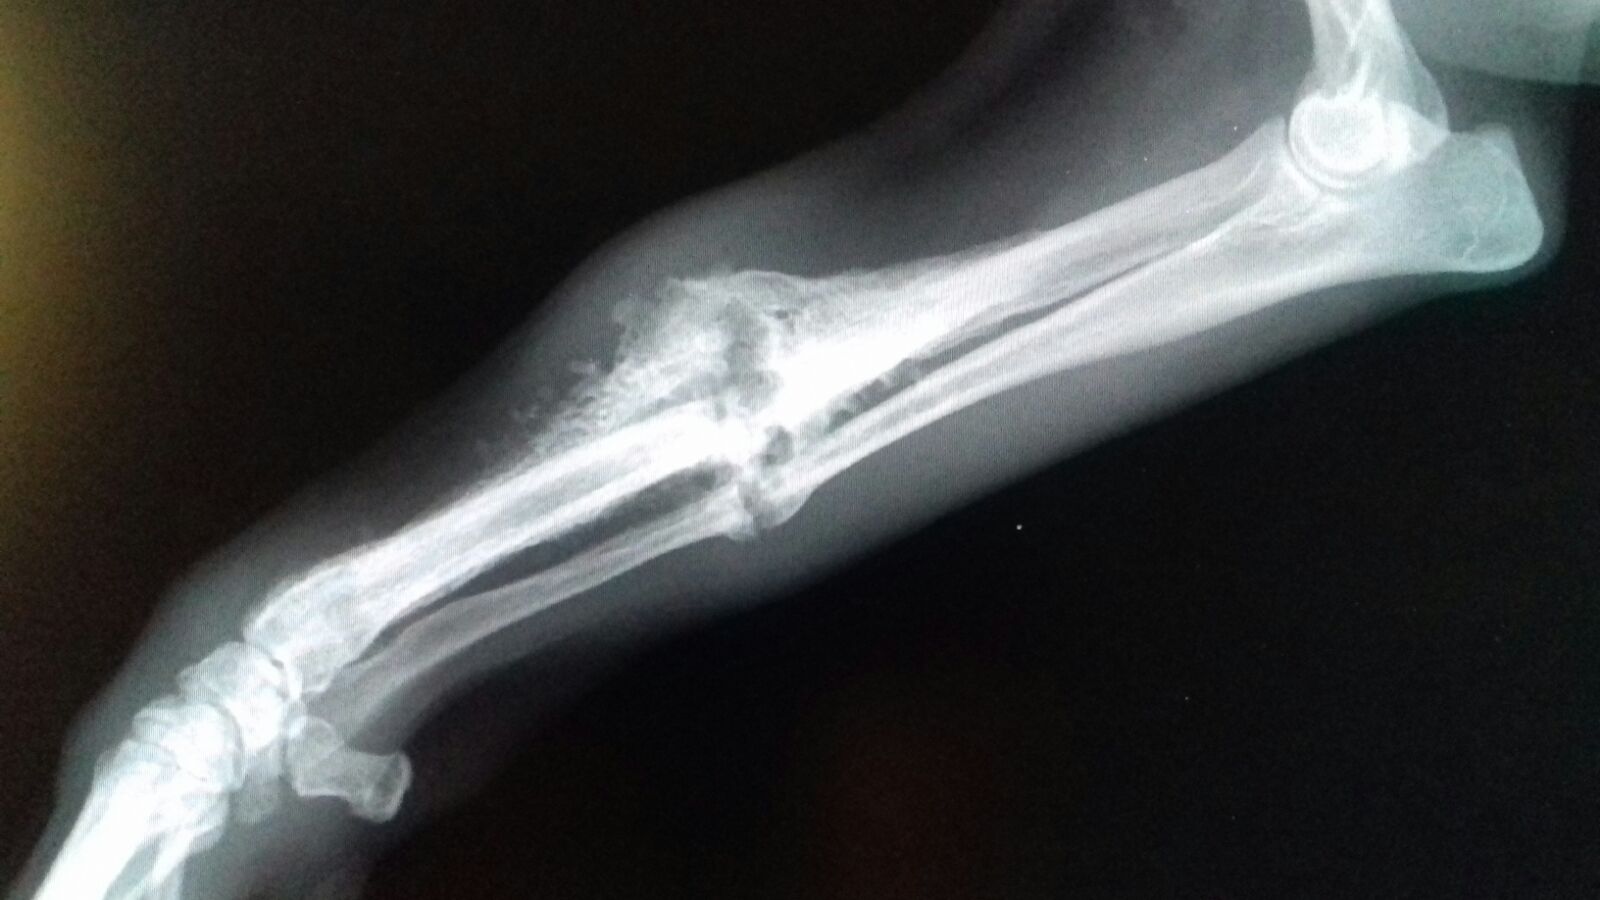

Im Rahmen der Kastration wurde auch Ricardas rechtes Vorderbein geröntgt. Die italienischen Tierärzte möchten nicht mehr daran rühren, aber wir lassen die Röntgenaufnahmen noch in Deutschland von einem Spezialisten für Orthopädie begutachten und hoffen, dass der lieben Hündin doch noch geholfen werden kann!

Ricardas gebrochenes Bein wird am 19.04. durch eine Operation stabilisiert. Damit stehen ihre Chancen sehr gut, dass sie ihr Bein bald wieder vollständig und schmerzfrei belasten kann!